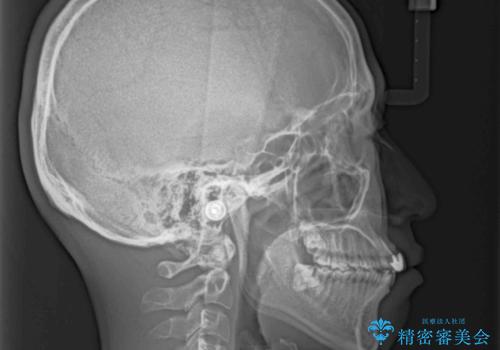

- 前歯の歯並びと不自然な色をした前歯のクラウンを気にして来院された患者様です。

上下前歯の歯列不正はインビザラインにより歯列を整え、その後に、前歯をオーダーメイドタイプのオールセラミッククラウンにて補綴治療することとしました。

初診時には、歯並びを整えることのみを検討されていましたが、歯列が整うにつれて不自然な色合いが気になるようになり、矯正治療を行ってから補綴治療をする計画を受け入れてくださいました。